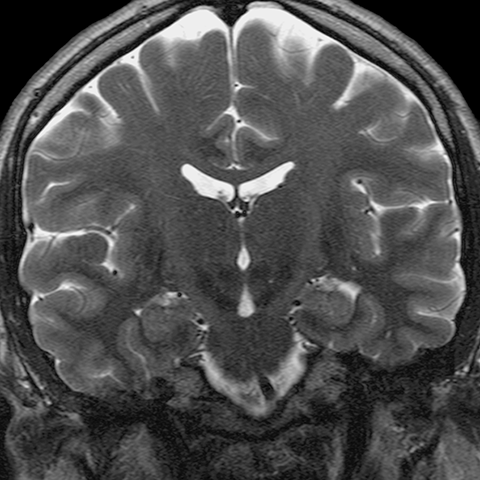

Tentorial Incisura [4 of 8]